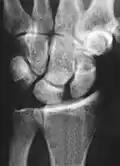

Static scapholunate dissociation -